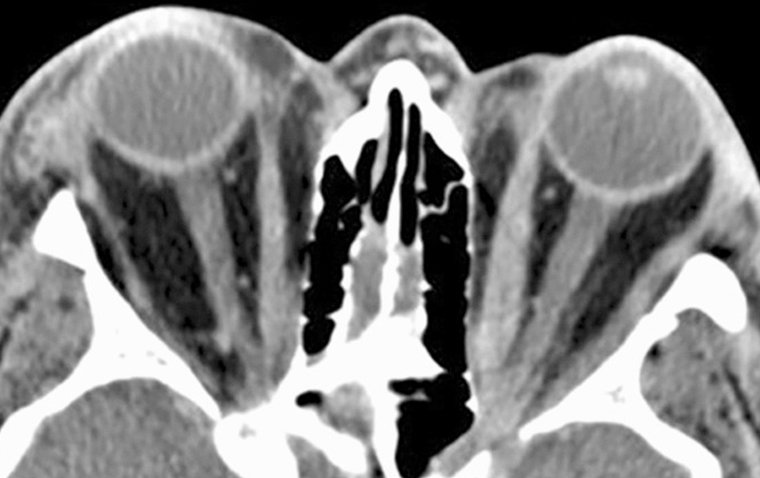

Своевременная и точная диагностика признана критически важной для эффективного ведения DON. Офтальмологи применяют различные методы, включая тесты на остроту зрения, оценку движений глазных яблок и методы визуализации, такие как компьютерная томография (КТ) и магнитно-резонансная томография (МРТ). Указанные исследования позволяют оценить степень вовлечения орбиты и компрессии зрительного нерва, что способствует выбору оптимальной тактики лечения.